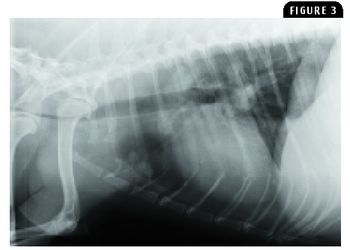

A 3-year-old male non-castrated English Bulldog was admitted to the Veterinary Medical Center because of intermittent episodes of gross hematuria of two months' duration.